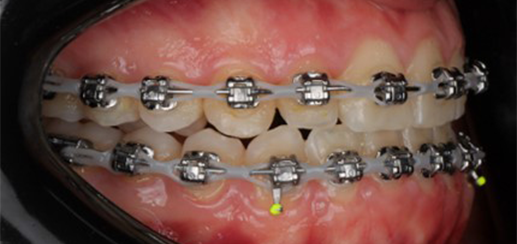

Initial leveling in the maxillary arch was carried out with a 0.014 CuNiTi archwire. This was followed by a 0.018 CuNiTi wire, with stoppers positioned mesial to the molars and activated to provide protrusion of incisors. The mandibular arch was then bonded and initial alignment was achieved with a 0.014 CuNiTi wire, then both jaws are progressing to 0.014 × 0.0275 CuNiTi and subsequently 0.018 × 0.0275 CuNiTi for torque control.

Finishing was completed with a 0.018 × 0.0275 TMA archwire in conjunction with Class III elastics.